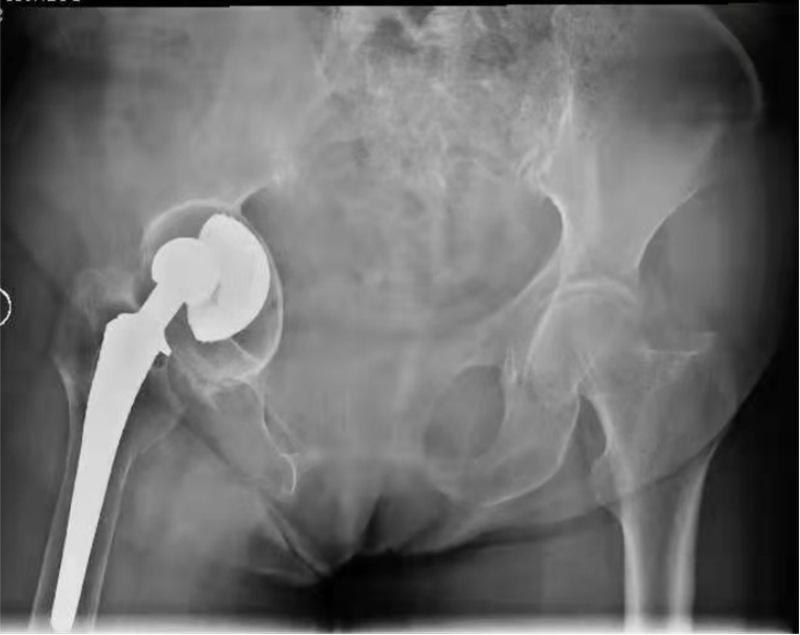

患者女性,7岁,右侧全髋关节置换术后16年,髋臼侧假体松动移位,合并严重的骨缺损和右下肢短缩(图5),诊断为“右髋关节置换术后假体无菌性松动”。手术前通过对CT影像进行降噪、分割、骨缺损范围识别后,对骨缺损修复和髋臼假体位置进行3D规划,手术由田华主任和李锋教授共同完成(图6)。

图5 患者术前X光片,右髋置换术后,现假体松动、严重髋臼侧骨缺损

图8 患者术后X光片,补块和假体位置满意,精准实现了术前规划